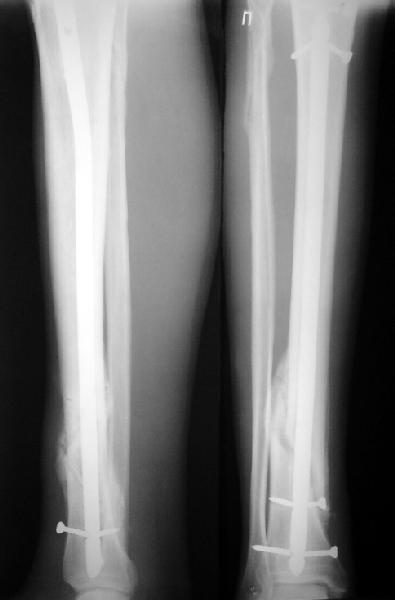

На мой взгляд, на снимках, приведённых Вами - неправильно сростающийся перелом дистальной трети большеберцовой кости, состояние после остеосинтеза интрамедуллярным гвоздём.

Как Вы пишите снимок под номером 1 - менсяц после операции, под номером 2- два месяца после операции.

Вы не послали послеоперационный снимок, поэтому трудно судить о состоянии редукции после операции.

Установка с медиальной стороны гвоздя в области дистального фрагмента дополнительного шурупа помогло бы Вам репонировать и удержать перелом в анатомическом положении, предотвратило варусную деформацию и смещение по ширине.

I think that the X-Rays show S/P IMN of Spiral # of the Distal Tibia consoles in misalignment.

You wrote that a picture number 1 - f month after the surgery, and number 2-two months after the surgery.

You have not sent a postoperative X-Rays; so it's impossible to discuss about the condition of a reduction after operation.

Let to express concerning technique of operation my opinion... Insertion of a screw to medial side of a nail in distal fragment would help you to reduction and to keep this fracture in anatomic position has prevented varus deformity and displacement on width. By the way, if it is possible send a postoperative picture.